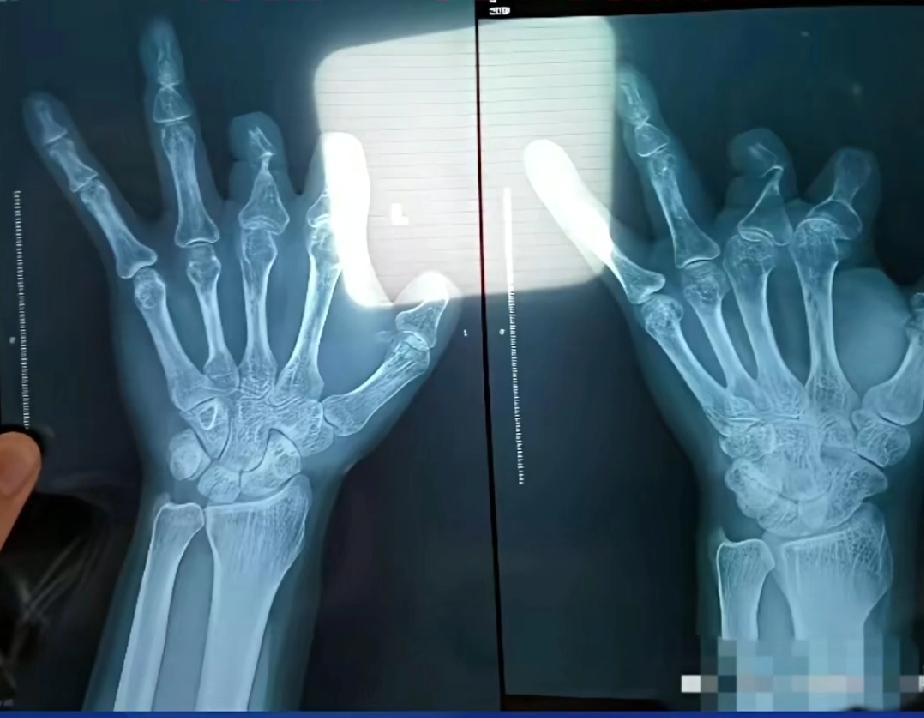

郑大一附院的王福建医生,简直就是恶魔,为了收到高额回扣,对部需要植入器械的手术,将器械扔进垃圾桶,把费用记在病人身上,以便边收取回扣,他为了不被病人在复查X光时发现,竟然将金属片放置患者体内,制造假象,防止病人发现,真是丧心病狂,几年时间他对94名患者,虚假收取高价微血管吻合装置费用,收医疗器械高额回扣。